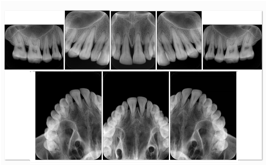

Intra-oral radiography typically involves acquisition of multiple images of various parts of the dentition. Many digital radiographic systems offer customized templates that are used for displaying the images in a study on the screen. These templates may also be referred to as mounts or view sets. The Structured Display Object represents a standard method of encoding and exchanging the layout and intended display of Structured Displays. A structured display object created in this manner could be stored with a study and exchanged with images to allow for complete reproduction of the original exam.

1. A patient visits a General Dentist where a Full Mouth Series Exam with 18 images is acquired. The dentist observes severe bone loss and refers the patient to a Periodontist. The 18 images from the Full Mouth Series along with a Structured Display are copied to a DICOM Interchange CD and sent with the patient to see the specialist. The Periodontist uses the CD to open the exam in his Dental Radiographic Software and consults via phone with the General Dentist. Both are able to observe the same exam showing the images on each user's display using the exact same layout.

Intra-oral Full Mouth Series Structured Display

Figure OO-1. Intra-oral Full Mouth Series Structured Display